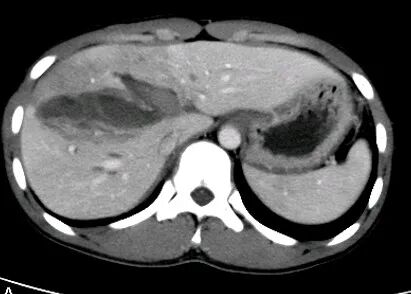

胃癌

进展期胃癌CT检查有利于观察病变的侵犯范围和淋巴结转移情况

早期胃癌多数病人无明显症状,少数人有恶心、呕吐或是类似溃疡病的上消化道症状。疼痛与体重减轻是进展期胃癌最常见的临床症状。病人常有较为明确的上消化道症状,如上腹不适、进食后饱胀,随着病情进展上腹疼痛加重,食欲下降、乏力。

根据肿瘤的部位不同,也有其特殊表现。

贲门胃底癌可有胸骨后疼痛和进行性吞咽困难;幽门附近的胃癌有幽门梗阻表现;肿瘤破坏血管后可有呕血、黑便等消化道出血症状。

腹部持续疼痛常提示肿瘤扩展超出胃壁,如锁骨上淋巴结肿大、腹水、黄疸、腹部包块、直肠前凹扪及肿块等。

晚期胃癌病人常可出现贫血、消瘦、营养不良甚至恶病质等表现。